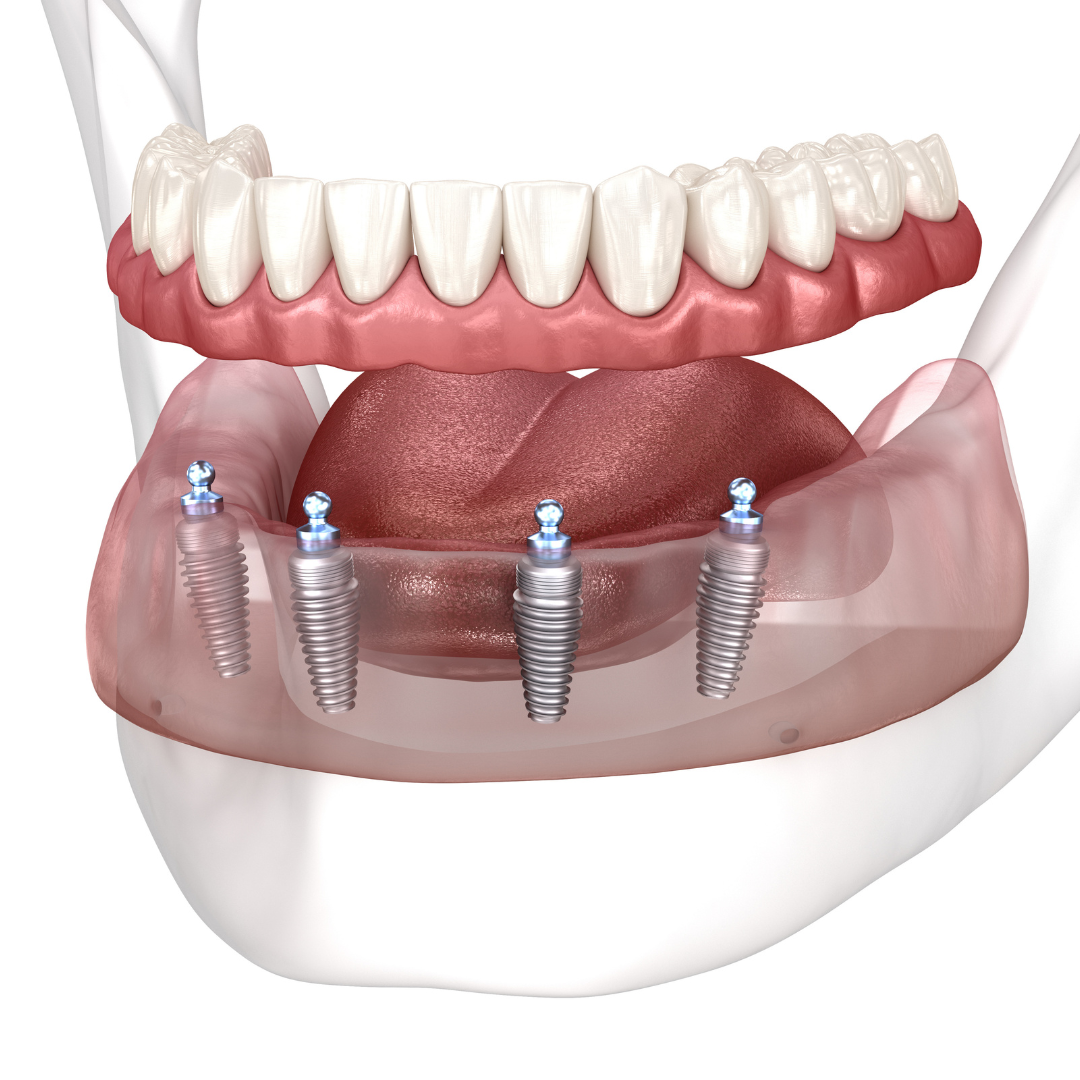

Every single dental implant consists of three parts - the implant, the abutment, & the crown. The implant is made of medical grade titanium. This part is surgically placed into the patient’s jaw bone and left to heal for 4-6 months afterwards.

This implant piece acts as the foundation for the rest of the tooth. Once the bone around the site has healed, the abutment and crown are placed on top of the implant. The end result is a beautiful, natural-looking new tooth!

Few people will ever be able to tell the difference between your implants and your real teeth.